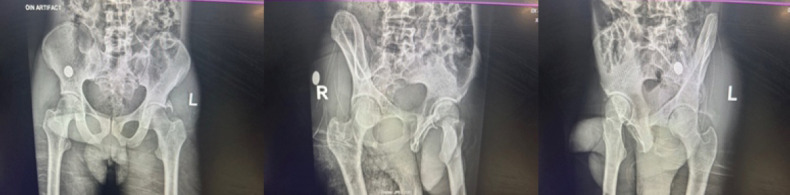

Introduction: Asymmetrical hip dislocations are rare injuries. The native hip joint is inherently stable, so both joints will dislocate in a high-energy setting. Therefore, it is imperative to exclude other associated injuries and fractures and ensure both hips are reduced timeously.

Case report: We present a rare case of a 46-year-old male patient who presented with asymmetrical complex hip dislocations following a pedestrian-vehicle accident. Both hips were reduced; however, the left acetabulum posterior wall needed open reduction and internal fixation.